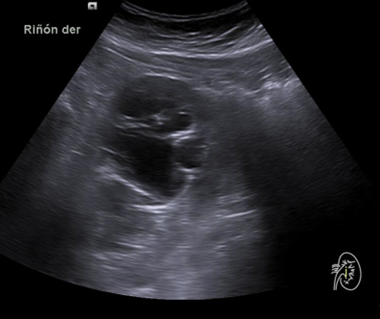

Hallazgos ecográficos

Riñón derecho 9,9 cm con morfología y ecogenicidad conservada. Presenta hidronefrosis grado III. No se identifica causa obstructiva.